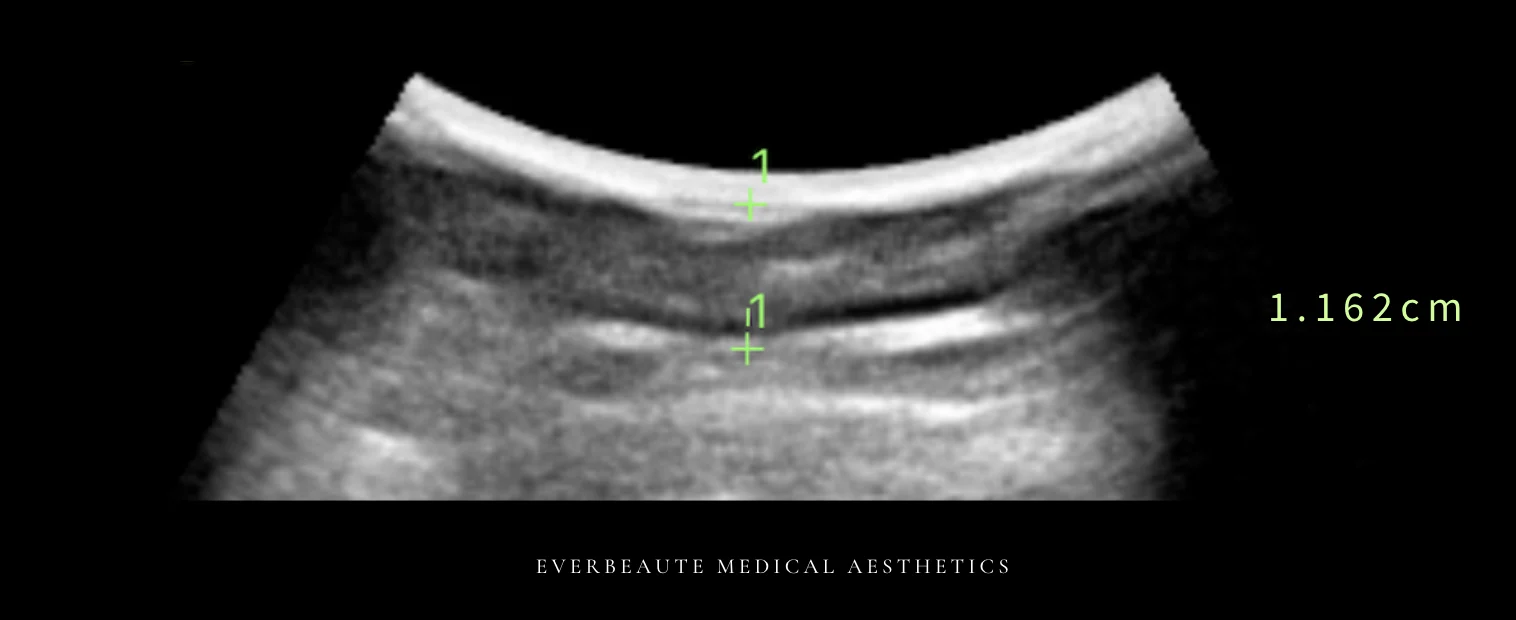

經術前與術後超音波檢查比較,上臂脂肪厚度由1.162公分減少至0.852公分,顯示脂肪厚度下降約26.7%,呈現顯著改善。